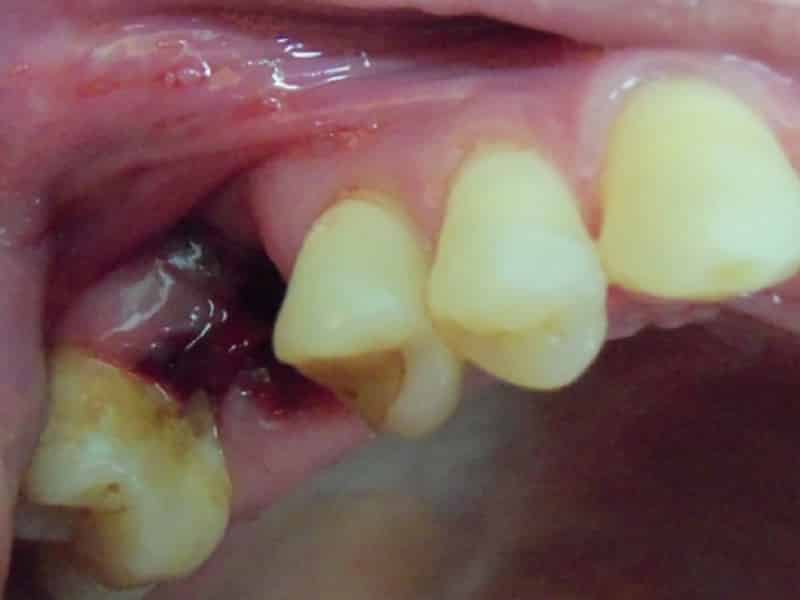

Чаще всего альвеолит наблюдается после удаления молярных зубов нижней челюсти. Это связано с более сложной анатомией этой области. Извлекать корни зубов из нижней челюсти труднее, особенно если они имеют деформации. Кроме того, инфекция, попавшая в рану, может быстро углубиться в мягкие ткани под воздействием гравитации и вызвать гнойное воспаление. Особенно это касается гноя после удаления зуба мудрости.

Нагноение после удаления зуба может указывать на различные постоперационные осложнения. К ним относятся:

- Альвеолит. Обычно он проявляется покраснением и отечностью лунки, а также острыми болями, кровотечением и образованием гнойных выделений. Альвеолит может сопровождаться ухудшением общего состояния, включая повышение температуры, дрожь, головные боли и чувство слабости.

Как видно, в большинстве случаев такие осложнения возникают из-за заражения лунки патогенными бактериями. Чтобы избежать этого, важно тщательно ухаживать за полостью рта. Чистка зубов должна проводиться осторожно, чтобы не повредить заживающую десну.

Также стоит помнить, что после удаления зуба в лунке остаются бактерии, что называется первичным инфицированием. Даже если стоматолог удалил зуб с корнями и гранулемами, инфекция не может быть полностью устранена. Тем не менее, ее распространение можно и нужно контролировать, что зависит от иммунной системы пациента и предпринятых им профилактических мер.